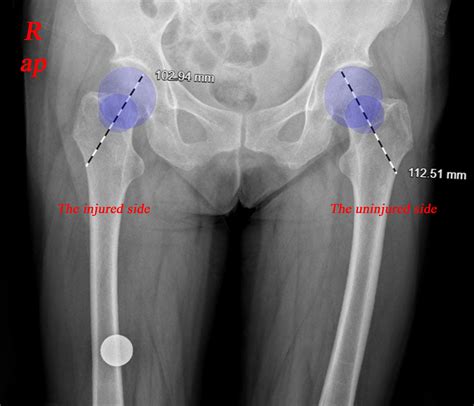

Diagnosing an impaction of fracture requires a thorough clinical evaluation and imaging studies. The diagnostic process typically involves the following steps:

• Imaging Studies: Radiographs (X-rays) are the initial imaging modality used to visualize the fracture. However, due to the complexity of impaction fractures, additional imaging studies such as computed tomography (CT) scans or magnetic resonance imaging (MRI) may be necessary to fully assess the extent of the injury.

In some cases, a CT scan may reveal the presence of bone fragments within soft tissues or other bones, providing a clearer picture of the impaction of fracture. MRI can be useful for evaluating soft tissue damage and assessing the integrity of surrounding structures.

Case Study 1: Femur Fracture

A 35-year-old male was involved in a high-speed motor vehicle accident. He sustained a severe femur fracture with impaction of the bone fragments into the soft tissue. The patient underwent surgical intervention with open reduction and internal fixation. Post-operative rehabilitation included pain management, range of motion exercises, and strengthening exercises. The patient made a full recovery and returned to his pre-injury level of function within six months.